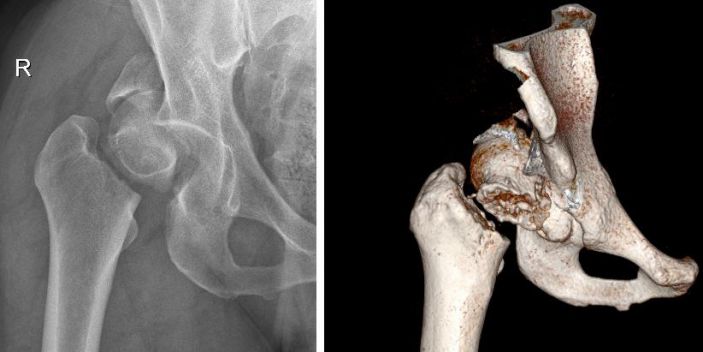

患者張某,男,37歲,燎原鎮人,體重180斤,4月19日騎自行車時不慎摔倒,右臀部着地,立即感到右臀部疼痛,右下肢活動障礙。在當地診所拍片顯示右股骨頸骨折,随來我院住院治療。經我院CT檢查,診斷爲右髋臼、右股骨頭、右股骨頸三處部位粉碎性骨折。

△術前